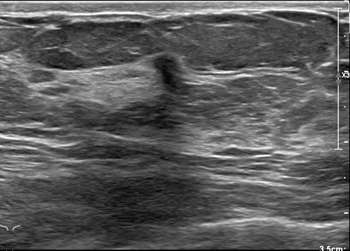

- Ultrasound (US):

Ultrasound has a higher sensitivity for detecting ILC than mammography, reported at 68-98%. A hypoechoic irregular mass with posterior shadowing is the most common imaging finding on US (60%)1. Less common findings are irregular shape and angular margins, or posterior shadowing without a discrete mass. About 10% of the time, ILC is not detected on ultrasound1.